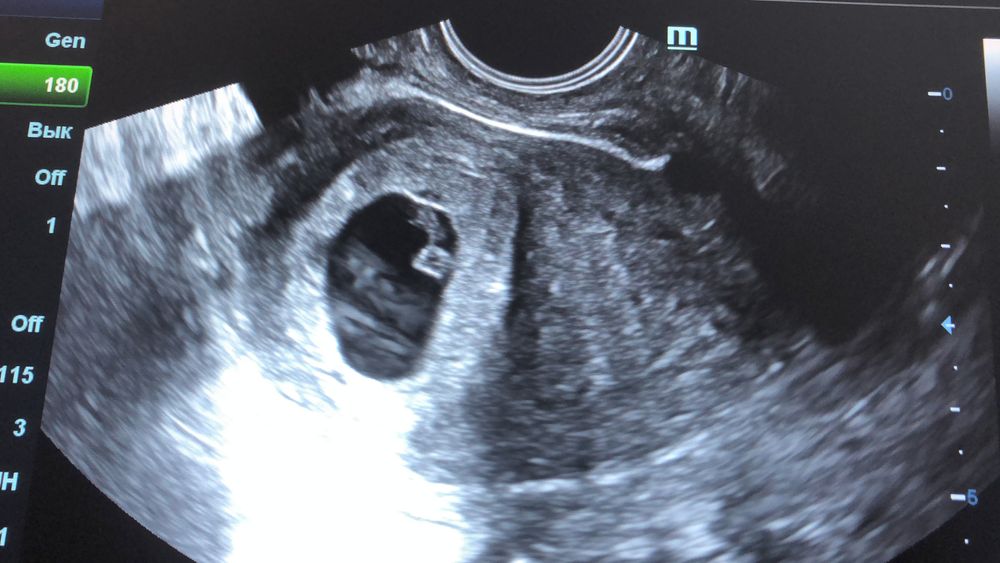

УЗИ 7 неделек 🥰

УЗИ, КТГ, доплерСегодня сходила на повторное УЗИ, счастью нет предела 😍 а когда включили звук, так сразу слезки потекли, как-то совсем трогательно 😅